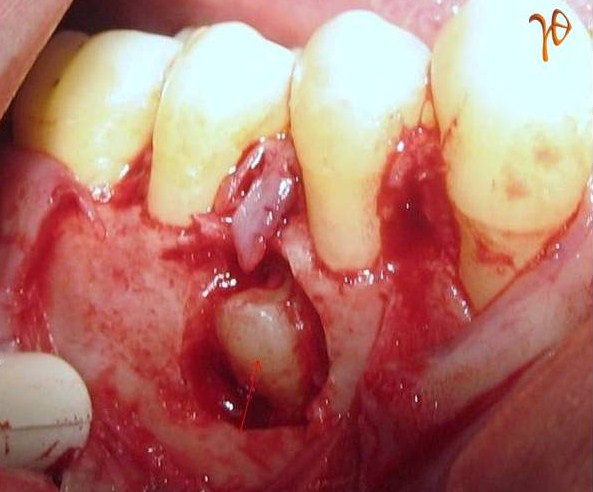

Εικ. 6 : Διεγχειρητική εικόνα του υπεράριθμου προγομφίου (βέλος). Ταυτόχρονη ακρορριζεκτομή του #13.

Εικ. 7 : Διεγχειρητική επιβεβαίωση της άκτινοδιαγνωστικής ένδειξης για απορρόφηση της ρίζας του #15 (βέλος).

Εικ. 8: Ο εξαχθείς υπεράριθμος με μορφολογία προγομφίου (supplemental form).